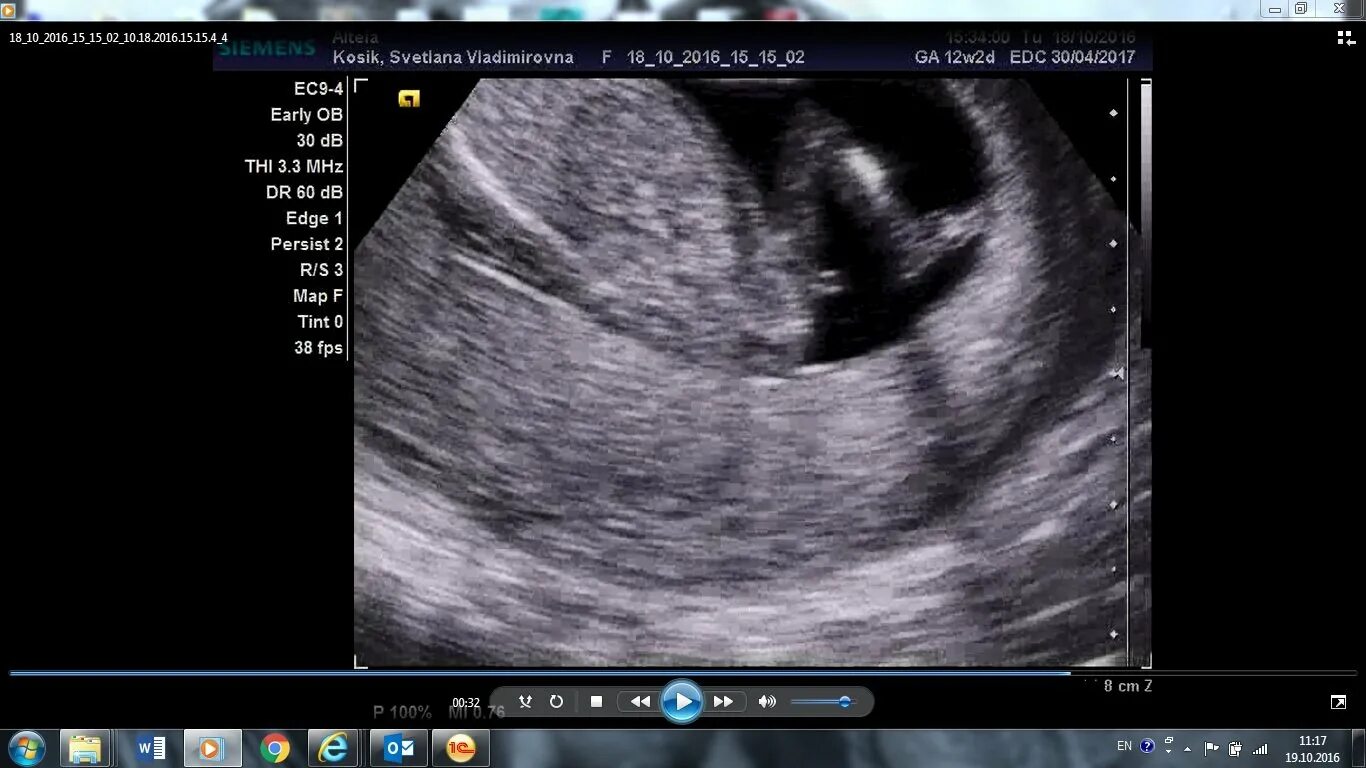

Второй скрининг 21 неделе